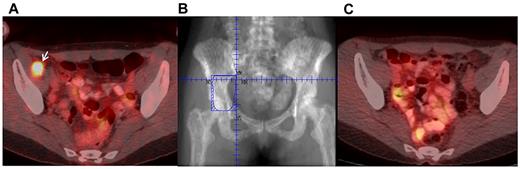

Given the wide variety of sites in which MS develops, imaging can facilitate diagnosis and monitor treatment response. MS often appears as a soft-tissue mass best suited to imaging by computed tomography (Figure 3A).67 Positron emission tomography can also be used (Figure 3C) and is particularly helpful for radiation therapy (RT) planning68 and monitoring response to treatment (Figure 4). When MS develops in the CNS, magnetic resonance imaging is useful.69 MS uniformly enhances with gadolinium, which should be administered when there are no contraindications (Figure 3B).67 The radiographic appearance of MS was recently reviewed by Fritz et al with many representative images provided.70 In our practice, computed tomography is routinely performed with consideration of a combined positron emission tomography scan if RT is planned.

Radiation therapy treatment field design and response. (A) MS in the right pelvis on positron emission tomography. (B) Radiation field treated to 24 Gy. Positron emission tomography scan 2 months after radiation, demonstrating resolution of lesion.